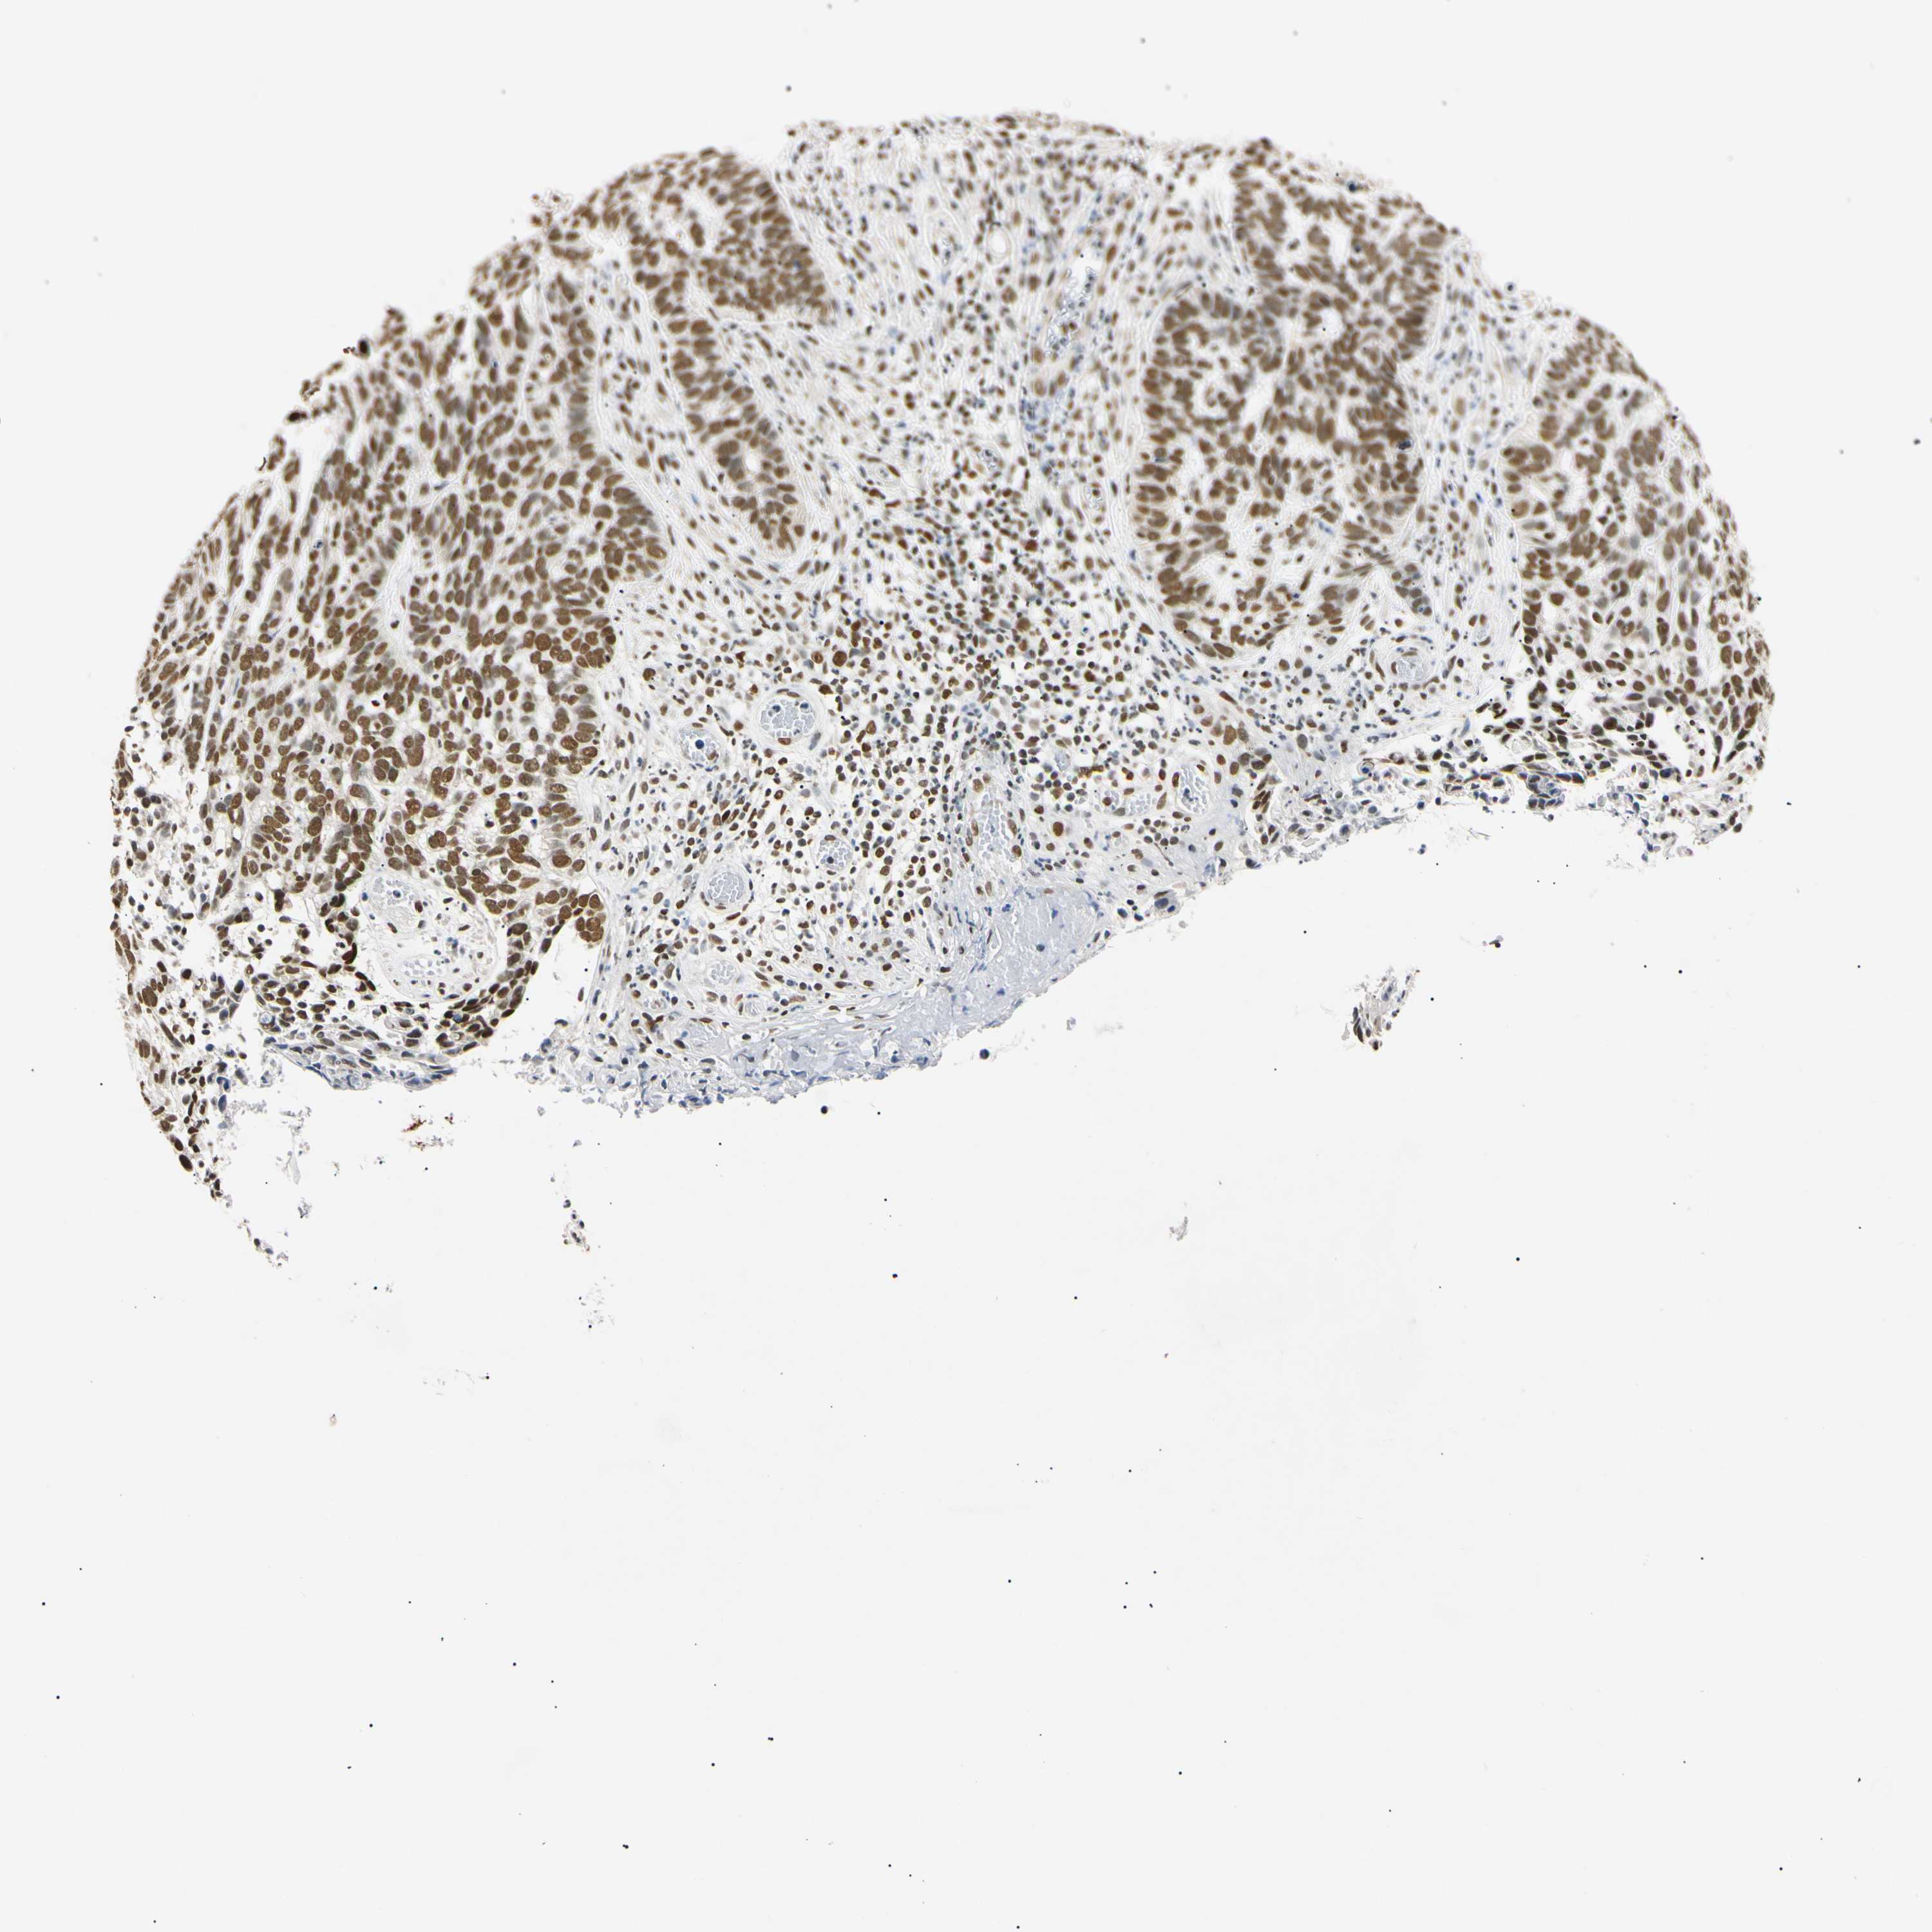

SKIN CANCER - Protein expressioni

A mouse-over function shows sample information and annotation data. Click on an image to view it in a full screen mode. Samples can be filtered based on level of antibody staining by selecting one or several of the following categories: high, medium, low and not detected. The assay and annotation is described here.

Antibody stainingi

Antibody staining in the annotated cell types in the current human tissue is reported as not detected, low, medium, or high, based on conventional immunohistochemistry profiling in selected tissues. This score is based on the combination of the staining intensity and fraction of stained cells.

Each image is clickable and will lead to virtual microscopy that enables deeper exploration of all samples and also displays staining intensity scores, fraction scores and subcellular localization as well as patient and tissue information for each sample.

Antibody HPA008751

Antibody CAB005227

Staining

High

Strong

>75%

Nuclear

Squamous cell carcinoma, NOS